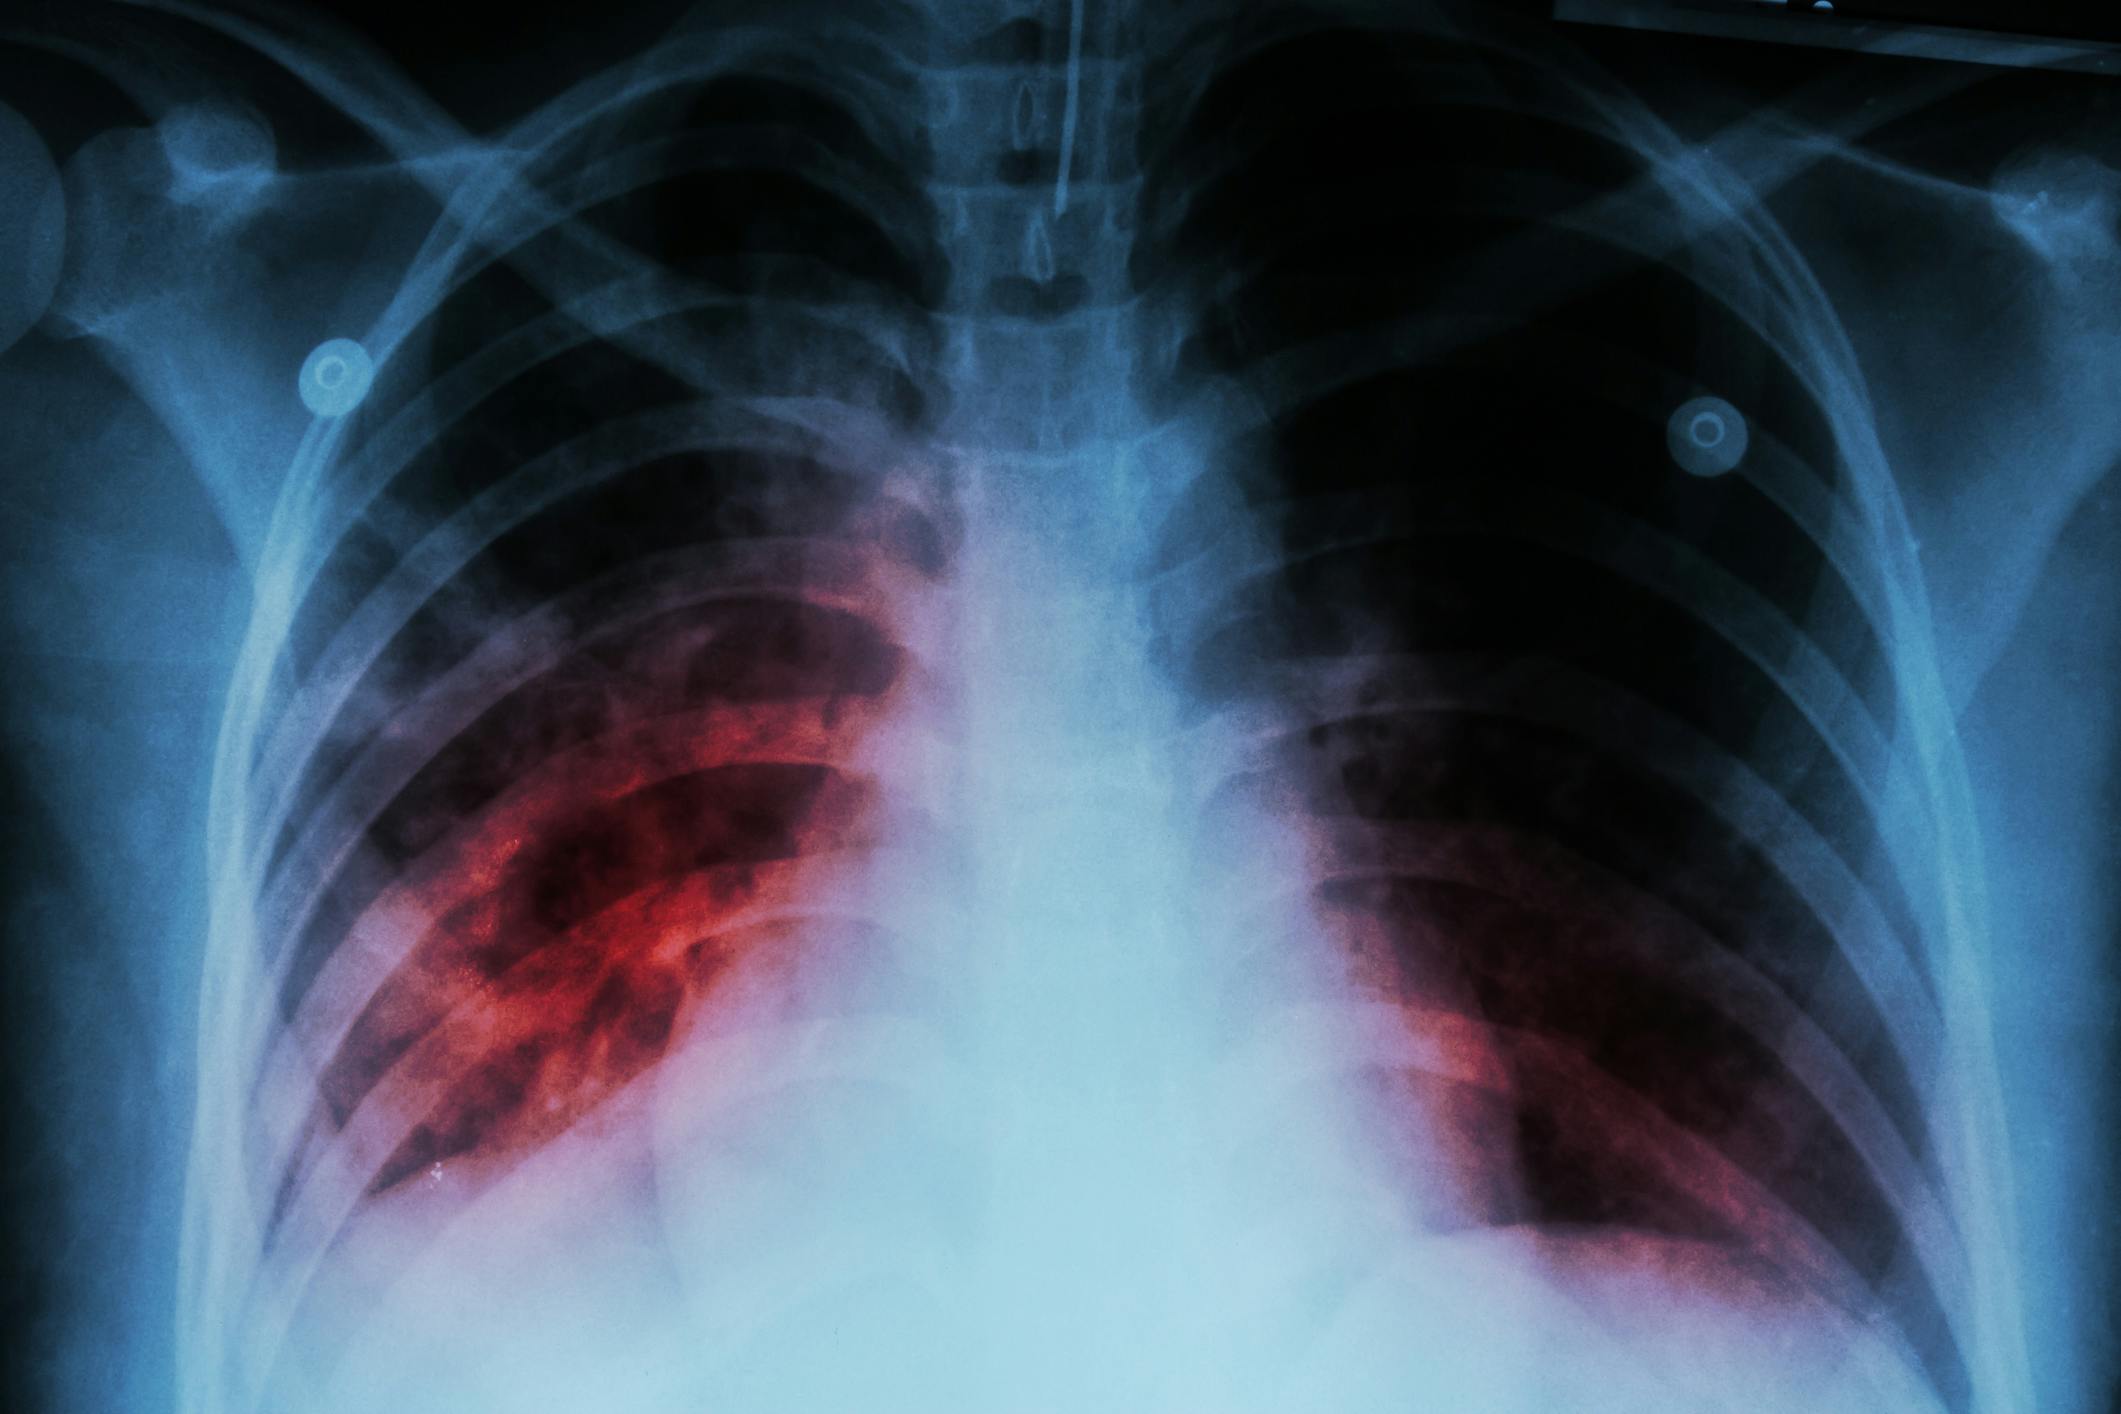

Study of More-Sensitive TB Test Found Positive TB Results Far More Prevalent Than Expected

- A highly sensitive TB test detected TB DNA in 12.3% of hospitalized patients, much higher than the 2% in controls.

- The study suggests the existence of a previously unrecognized form of TB, called paucibacillary TB, with bacterial levels too low for conventional detection.